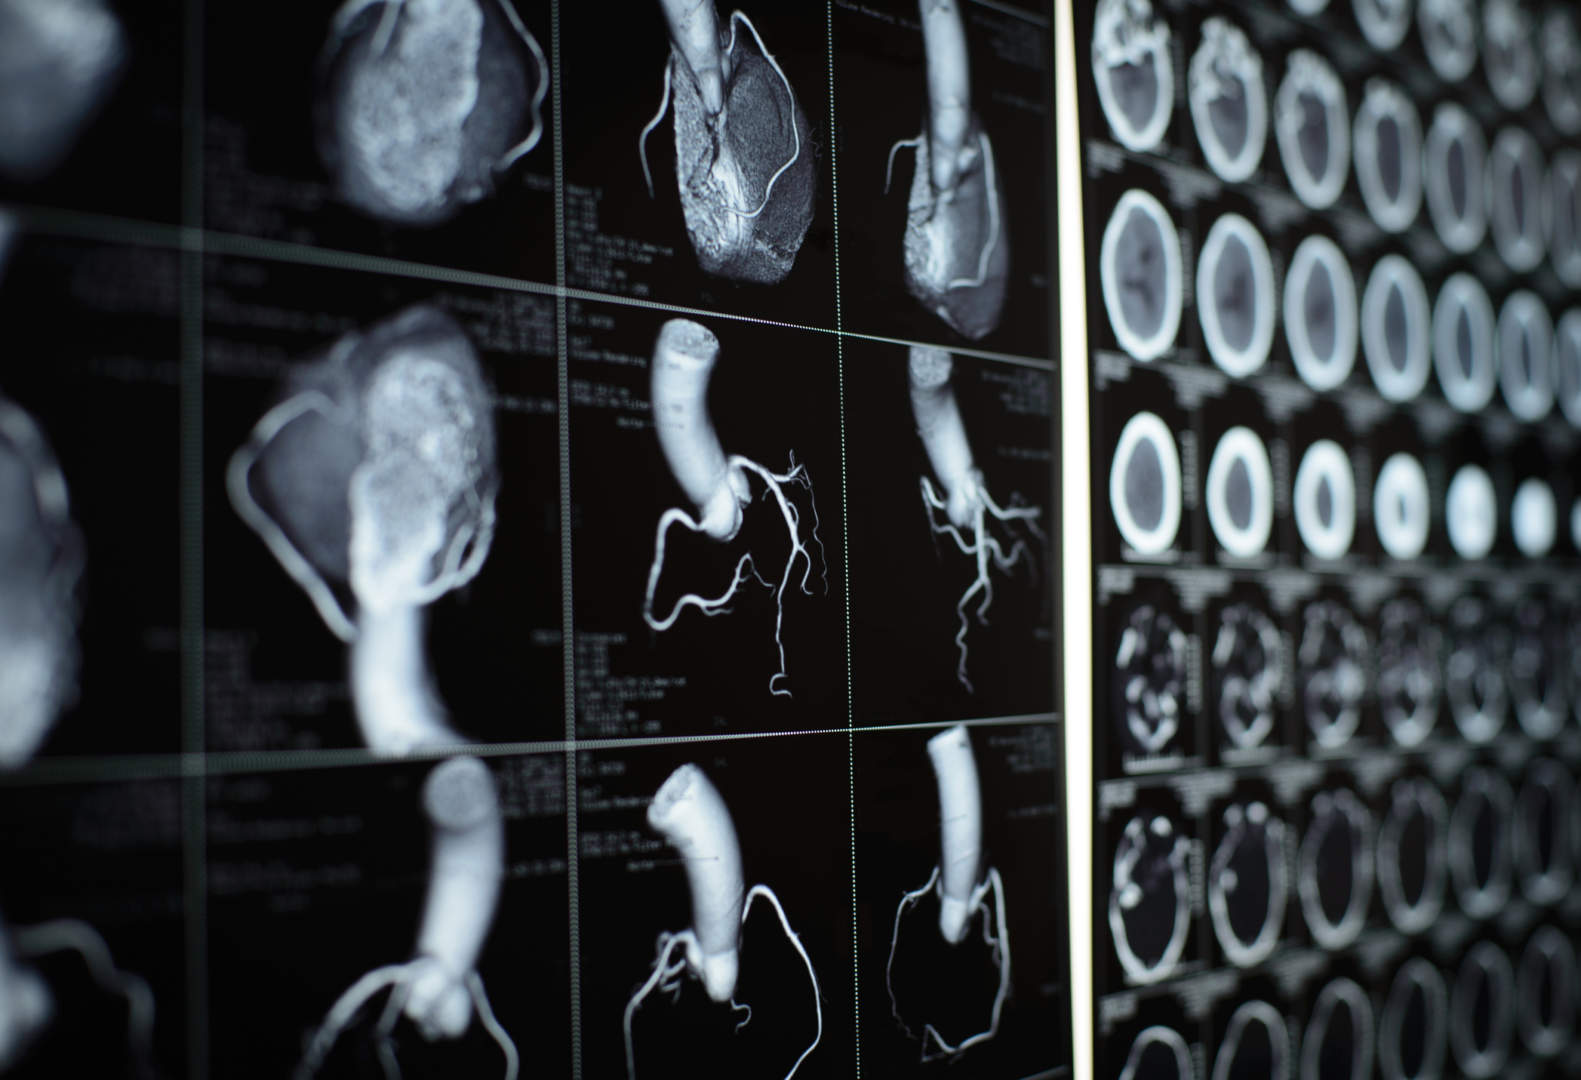

Ogni sospetta patologia cardiaca ha il suo esame specifico. Quello relativo alle malattie coronariche è la TAC cuore, esame diagnostico strumentale eseguito oggi con sempre maggiore frequenza. Si tratta di un esame di secondo livello, eseguito dal medico cardiologo in collaborazione con i radiologi.

In definitiva, la TAC cuore viene oggi considerata un esame di screening che ha soppiantato il tradizionale test da sforzo, ormai ritenuto troppo poco accurato per riconoscere la presenza di malattia: «Ci consente di capire – conclude la cardiologa – se il paziente è sano e non ha bisogno di terapie nell’immediato, se è molto malato e deve essere sottoposto a una coronarografia o a maggiori accertamenti, o – nella maggior parte dei casi – se deve semplicemente essere sottoposto a nuove terapie mediche o se si debbano aggiustare quelle già in essere per evitare che l’aterosclerosi coronarica progredisca nel tempo, causando un infarto».